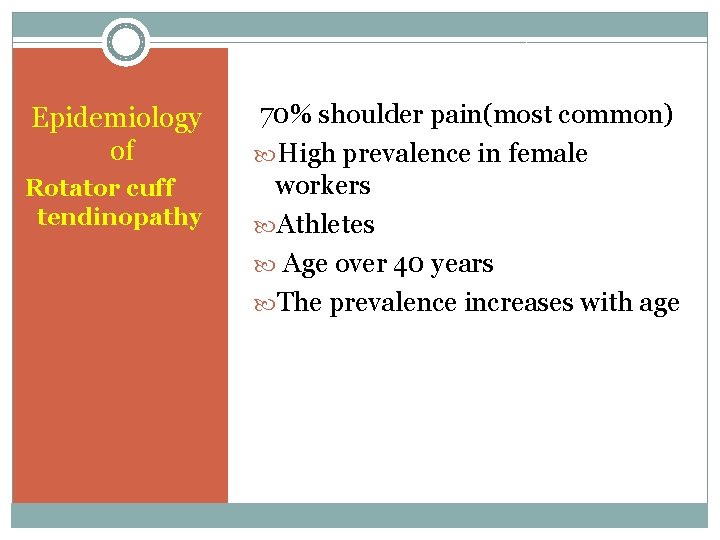

Epidemiology of Rotator cuff tendinopathy 70% shoulder pain(most common) High prevalence in female workers Athletes Age over 40 years The prevalence increases with age